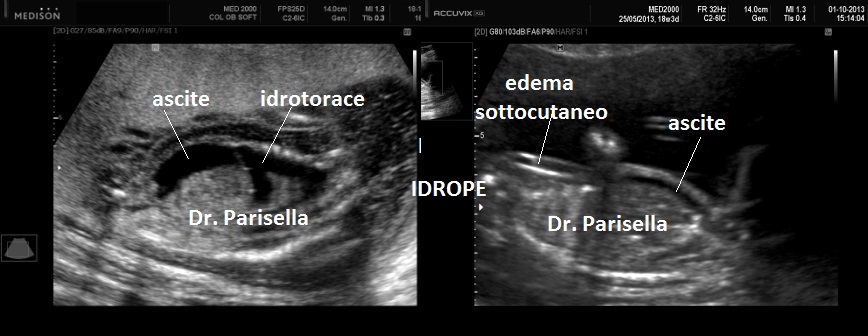

La Diagnosi Prenatale Ecografica si basa su:

3) Idrope.